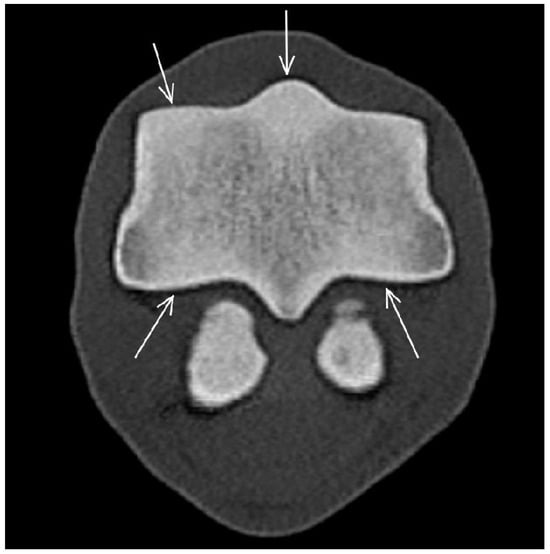

| Proximal sesamoid bone Medial/Lateral | |||

| Prominent vascular channels Thickening of axial/abaxial compact bone Increased attenuation in trabecular bone Modelling | Thickening of axial/abaxial compact bone Decreased signal intensity in trabecular bone Modelling | Prominent vascular channels Modelling | |

| Suspensory ligament branches | Asymmetry in size between medial and lateral branches Increased attenuation Enlargement of cross-sectional area | N/A | N/A |